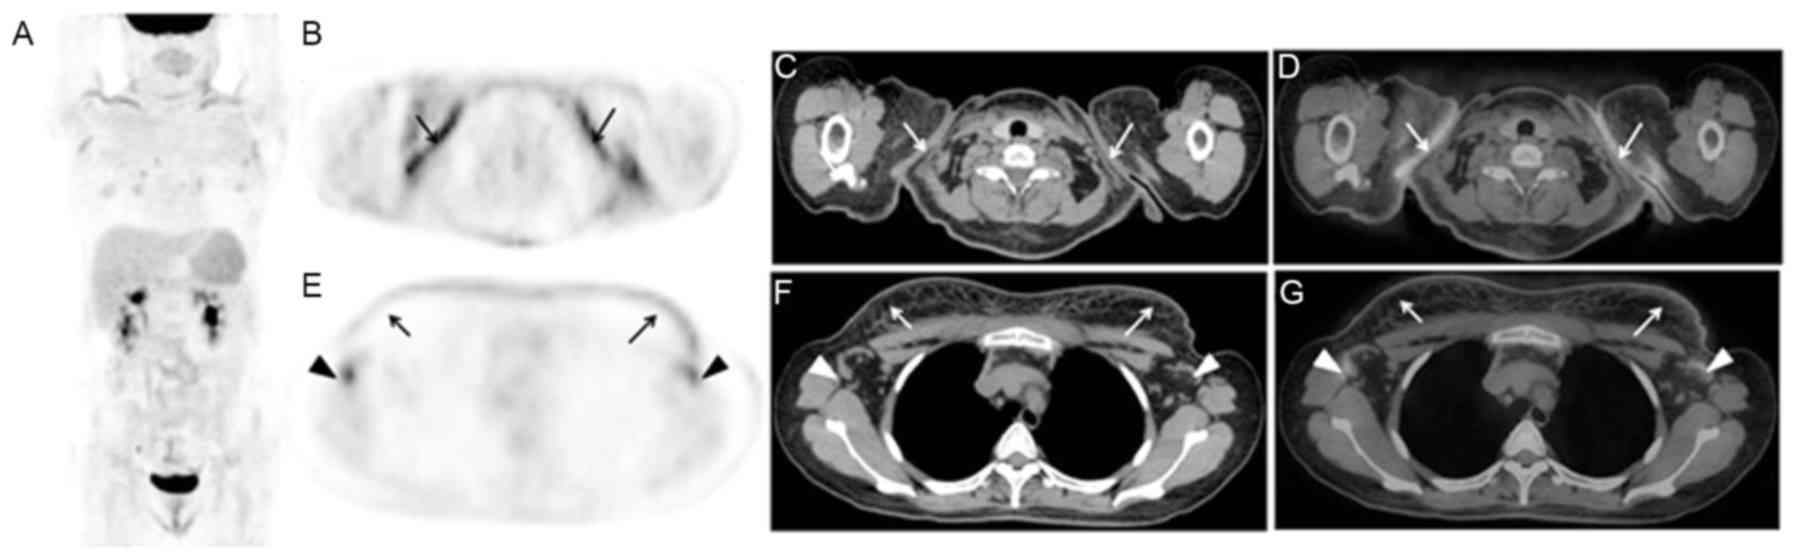

Based on the imaging features of this study, the roles of 18F-FDG PET/CT in AOSD were retrospectively investigated. Firstly, 18F-FDG PET/CT could display both anatomic and functional changes of AOSD, and evaluated the involved extent of AOSD. For example, as presented in Fig. 3, the case only displayed diffusely elevated FDG activity in bone marrow of whole body on PET/CT images. The case in Fig. 4 demonstrated that although multiple enlarged lymph nodes of the whole body with mildly increased radioactivity were displayed on PET/CT images, the benign diseases of lymph nodes such as inflammation rather than malignancies were diagnosed based on the size, morphology, density, and SUVmax of the lymph nodes in this case. However, for other cases, as presented in Figs. 5 and 6, which was difficult to make differential diagnosis with lymphoma. Secondly, it could guide the biopsy of tissues with abnormal FDG accumulation including lymph nodes, bone marrow, skin and other tissues. Regarding the cases in Figs. 5 and 6, the biopsies of the lymph nodes were performed under the guide of 18F-FDG PET/CT imaging, which contributed to suggest the proper lymph node applied for the biopsy. Finally, 18F-FDG PET/CT is helpful in the post-treatment evaluation of AOSD. Although these data weren't investigated in the present study, Choe et al (2) and Yamashita et al (17) identified significant improvements (decreased SUV level) in the initially abnormally sized radioactive lesions in the follow-up images of PET/CT.

Figure 6.

A 67-year-old female presented with fever (Tmax of 39.0°C) for 4 weeks, and anti-inflammatory therapy was invalid. 18F-FDG PET/CT imaging observed that diffuse FDG uptake by the spleen and bone marrow (A: MIP, triangle arrows), and multiple lymphadenopathy with abnormal FDG uptake in the cervical, supraclavicle, mediastinum and lung hilar regions (B and E, PET; C and F, CT; D and G, PET/CT; arrows). The pathology after the biopsy of the right supraclavicle lymph node (B-D; arrows) led to the diagnosis of non-specific inflammation. The bone marrow biopsy indicated non-specific and mild hyperplasia of hematopoietic cells, predominantly myeloid, and lymphocytes and plasma cells within normal range. During the follow-up, the lymph nodes of supraclavicle, mediastinum and lung hilar regions were significantly decreased or disappeared on chest CT images. 18F-FDG, fluorodeoxyglucose; PET, positron emission tomography; CT, computerized tomography; MIP, maximum intensity projection.